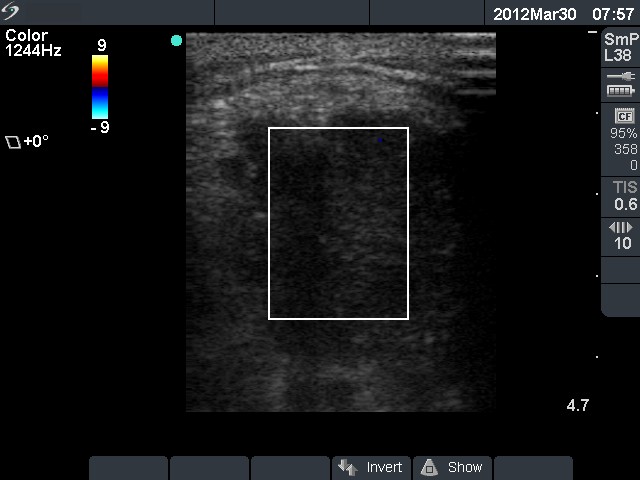

Ultrasonography. The left lobe and the isthmus were infiltrated by multiple hypoechogenic nodules. The transverse diameter of the thyroid was 8 cm, while the longitudinal diameter exceeded 20 cm.